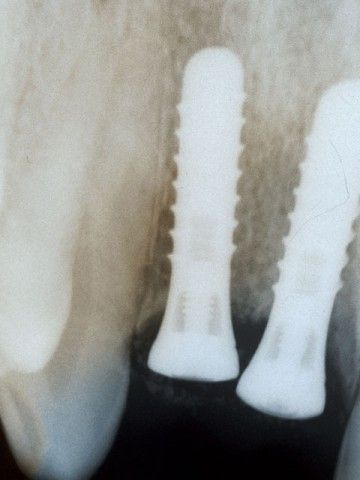

Από το 1992, ο χειρουργός οδοντίατρος Ιωάννης Μαρινάκης, στα Χανιά, ασχολήθηκε με τη χειρουργική τοποθέτηση εμφυτευμάτων και αναπλαστικών υλικών ιστικής και οστικής αναγέννησης.

Τη δεκαετία του 1990 αναπτύχθηκαν μέθοδοι με τις οποίες μπορούμε να επιτύχουμε μερική ανάπλαση των ιστών που συγκρατούν τα δόντια (περιοδόντιο) και μεγαλύτερη έως πλήρη ανάπλαση του φατνιακού οστού. Καθοριστικής σημασίας ήταν, αρχικά, η χρήση της ημιδιαπερατής μεμβράνης και στη συνέχεια των αυξητικών παραγόντων, προϊόντων υψηλής βιοτεχνολογίας.

Το περιστατικό στις φωτογραφίες είναι του 1998 και αφορά αποκατάσταση απώλειας δοντιών και οστού στην πρόσθια άνω περιοχή από τροχαίο ατύχημα: